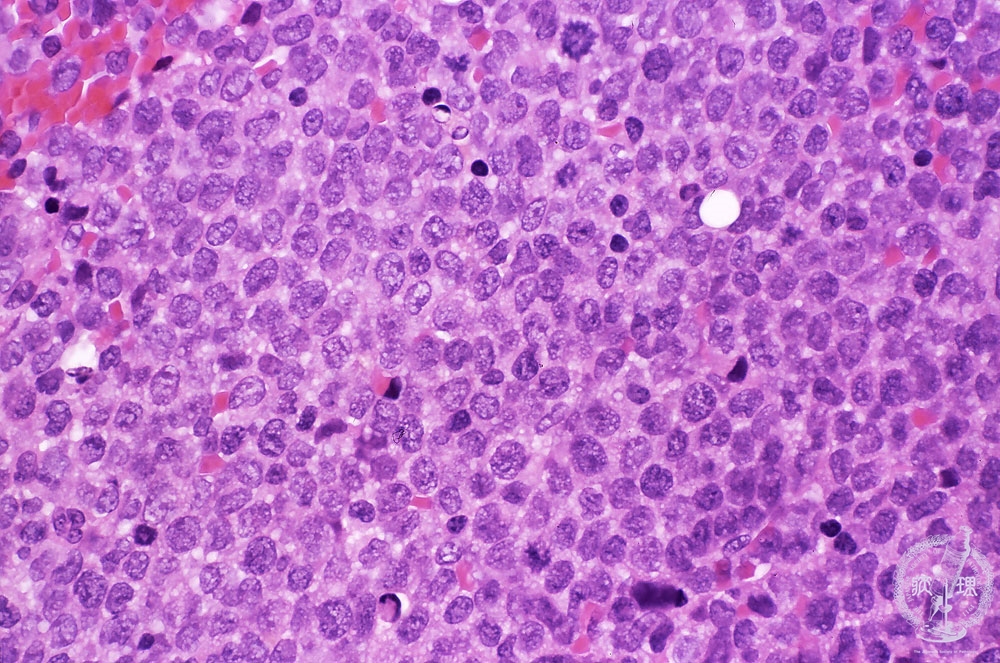

Microscopic image (H&E high power view): Diffuse proliferation of large myeloid blasts is found. These blasts have cytoplasmic granules. The same blasts resemble monoblasts with kidney-shaped nuclei.